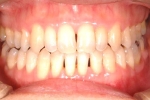

| 治療後3年経過時

| 治療前後の比較